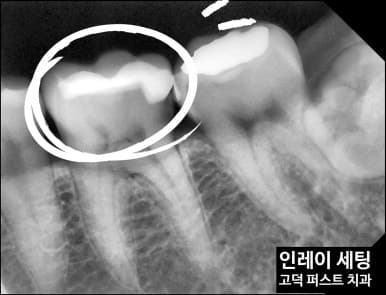

엑스레이 진단

엑스레이상 인레이 변연부의 불량이 명확히 보입니다. 경계 틈새로 충치균이 침투해 2차 우식이 형성되어 있습니다.